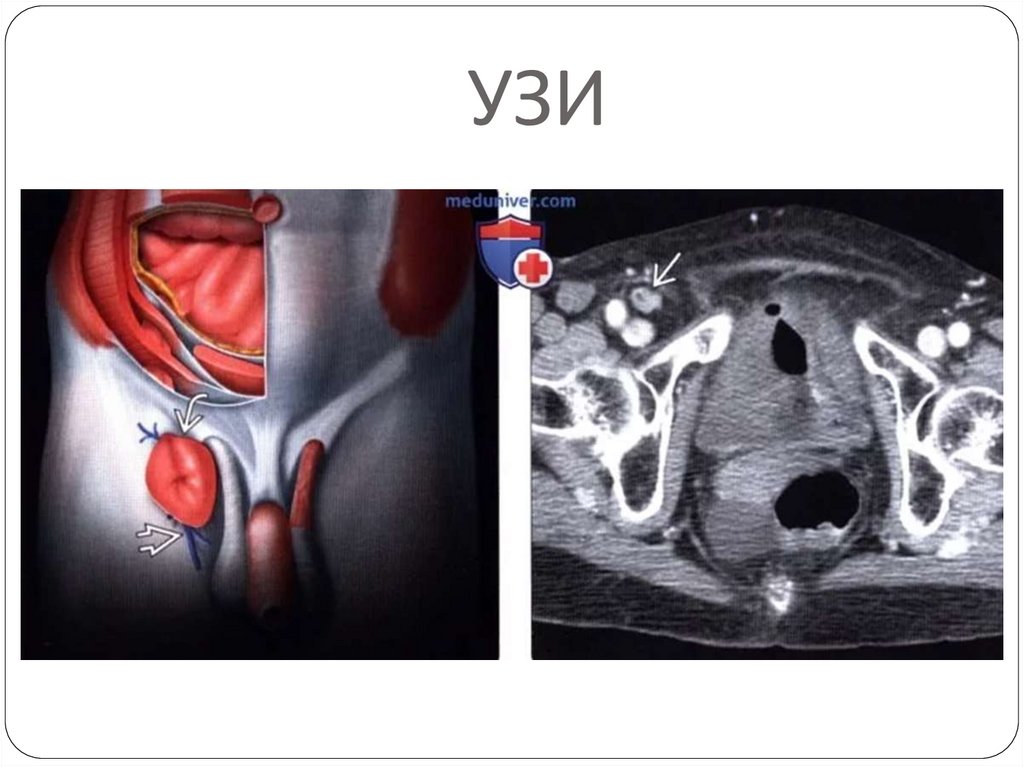

Среди инструментальных методов

диагностики ведущее значение имеет УЗИ:

Плюсы узи:

• диагностировать начальные формы грыж;

• идентифицировать их содержимое (особенно при

невправимых и гигантских грыжах);

• заподозрить наличие и вид скользящей грыжи.

УЗИ